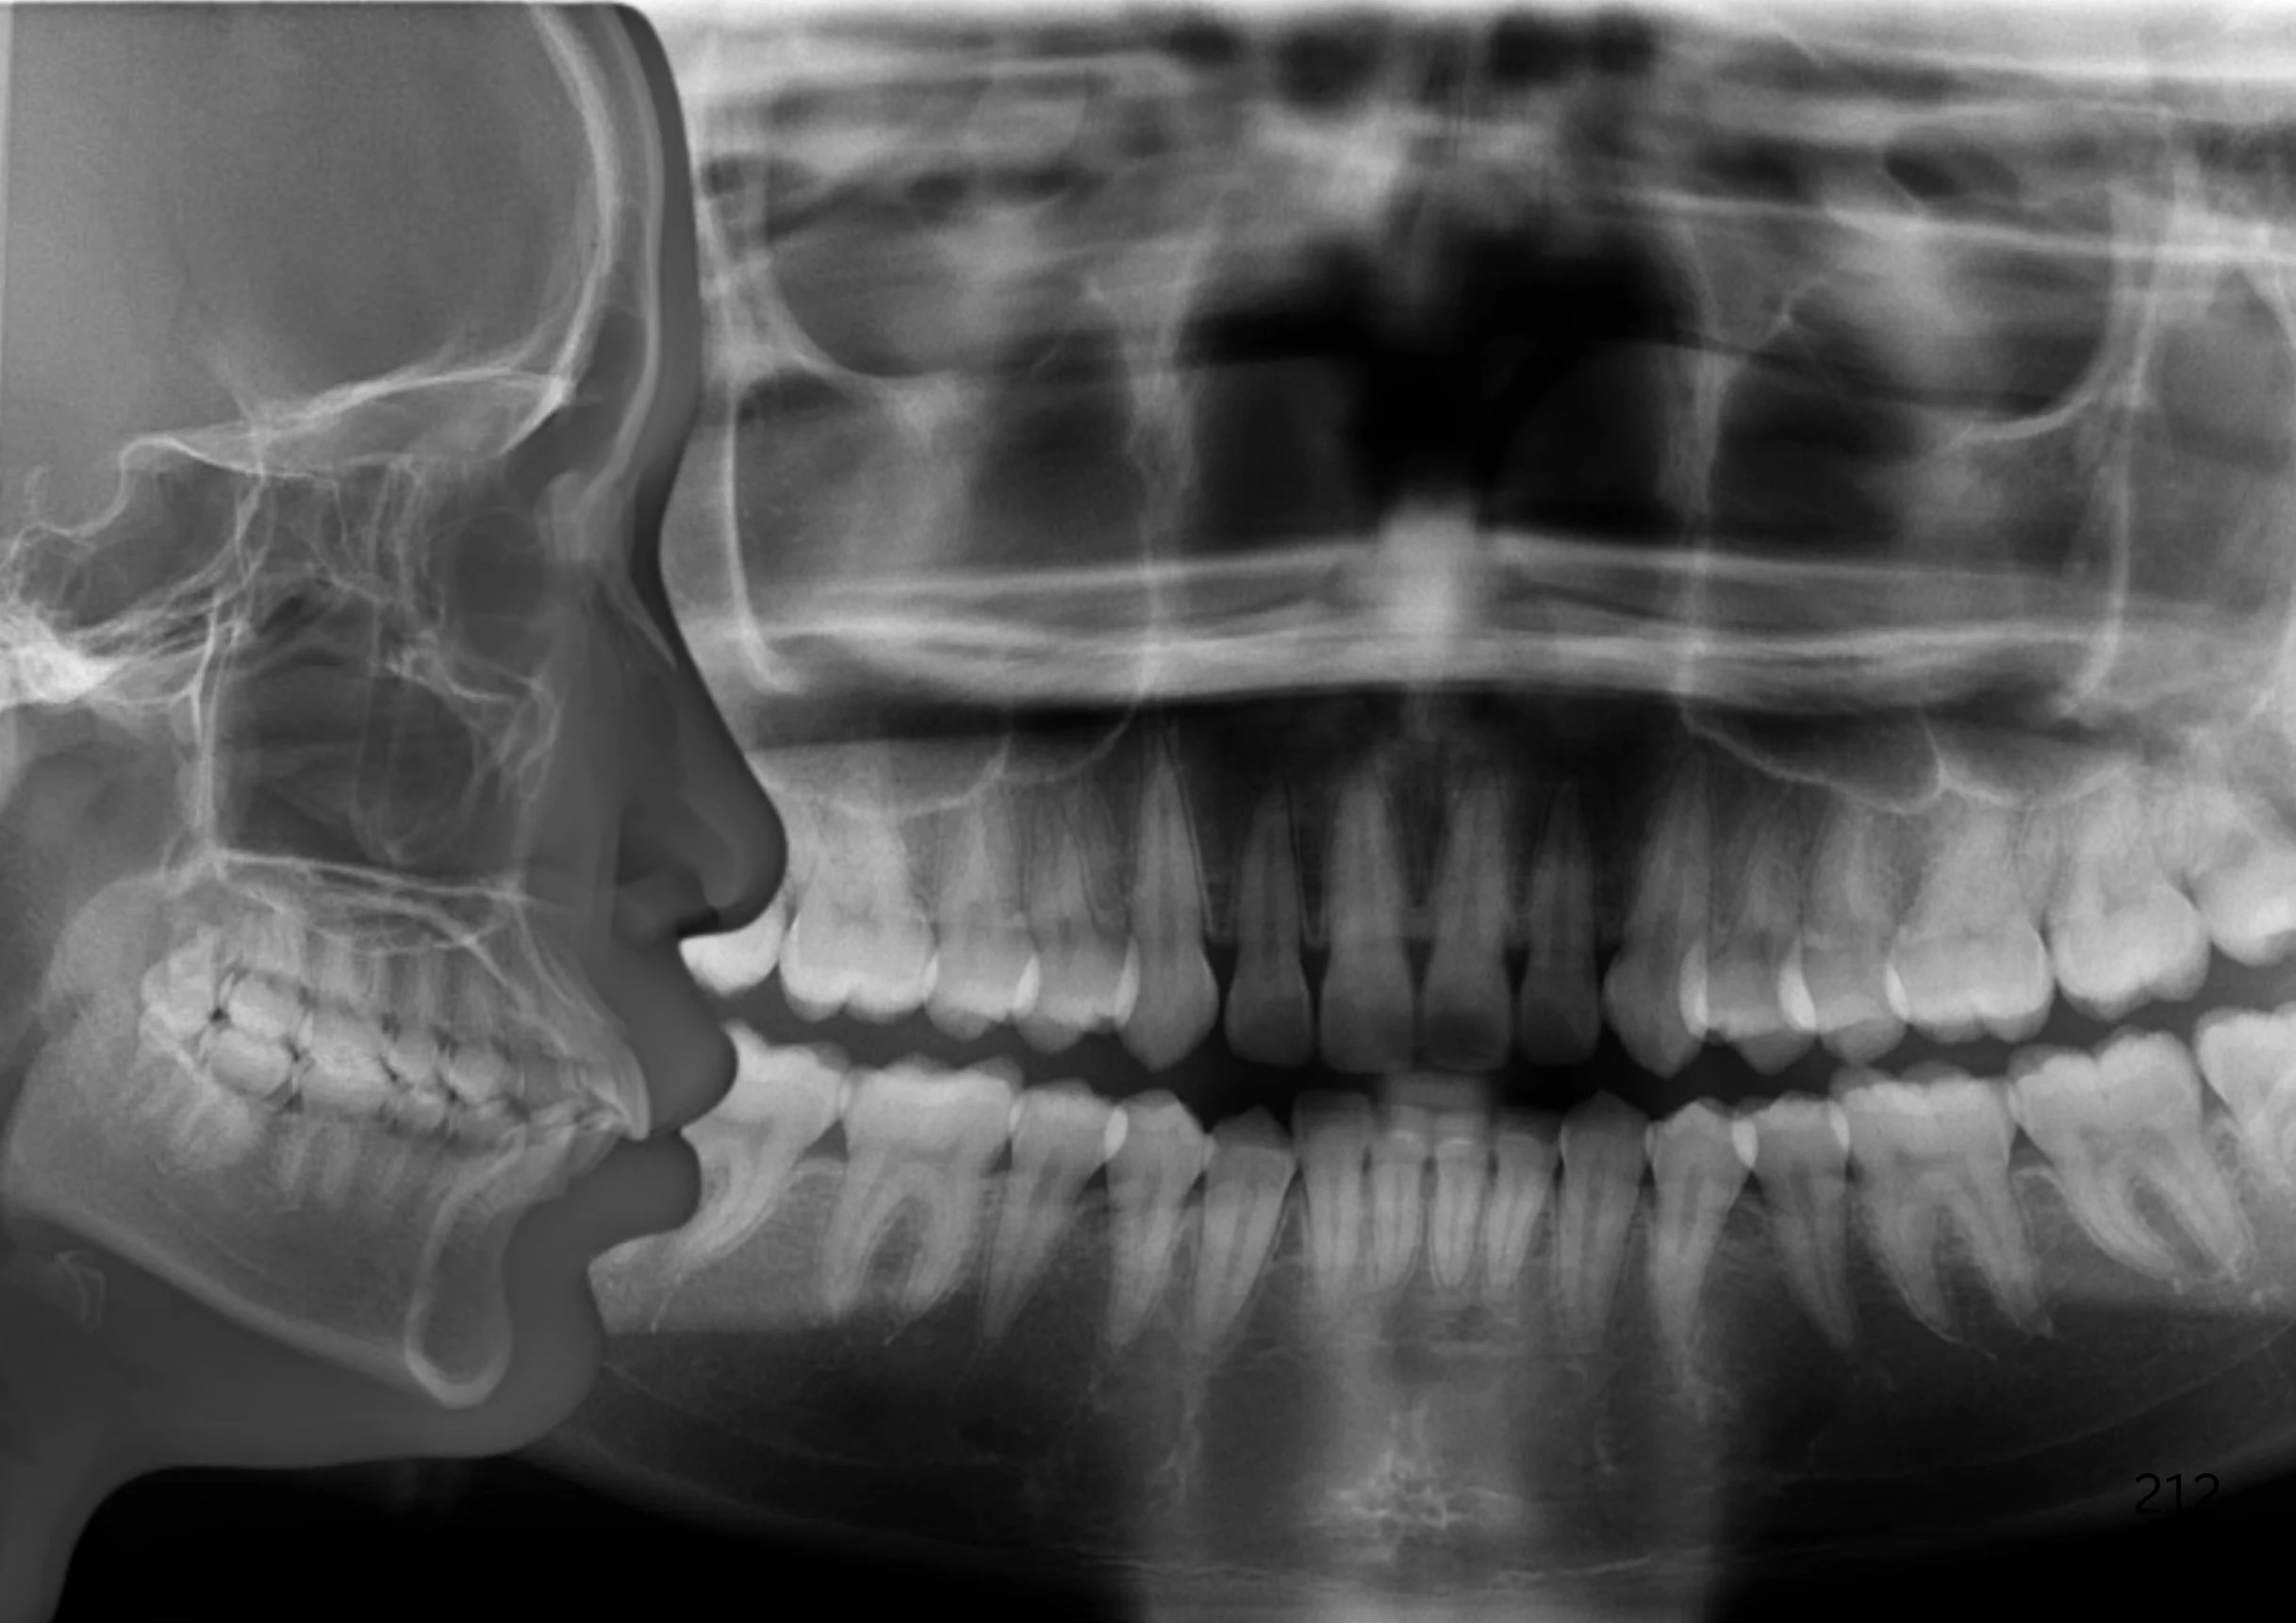

Before overcrowding treatment at SmileBox Clinic After overcrowding treatment at SmileBox Dental Clinic